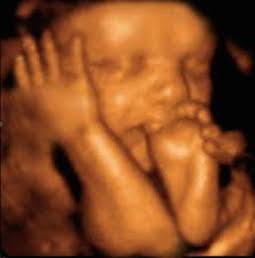

- Ciencia: Debatir el concepto «persona» es un argumento abstracto, el concepto «vida» no lo es. La ciencia lo afirma indiscutiblemente, en multitud de fuentes, que la vida comienza en la concepción. También es importante tener en cuenta la rapidez con que se desarrolla un niño dentro de la madre. Los hitos del desarrollo fetal del primer trimestre extraídos de la clínica Mayo incluyen:

Fertilización e implantación (el proceso comienza aproximadamente 2 semanas desde el último período menstrual). Semana 3 (5 semanas desde LMP): el cerebro, la médula espinal y otros órganos comienzan a formarse. Semana 4: (6 semanas desde LMP): las características faciales comienzan a aparecer, el corazón del bebé bombea sangre. Semana 9 (11 semanas a partir de la LMP): los genitales se desarrollan. El comienzo de la vida es un hecho indiscutible y es una medida efectiva y justa a partir de la cual se puede configurar la política.